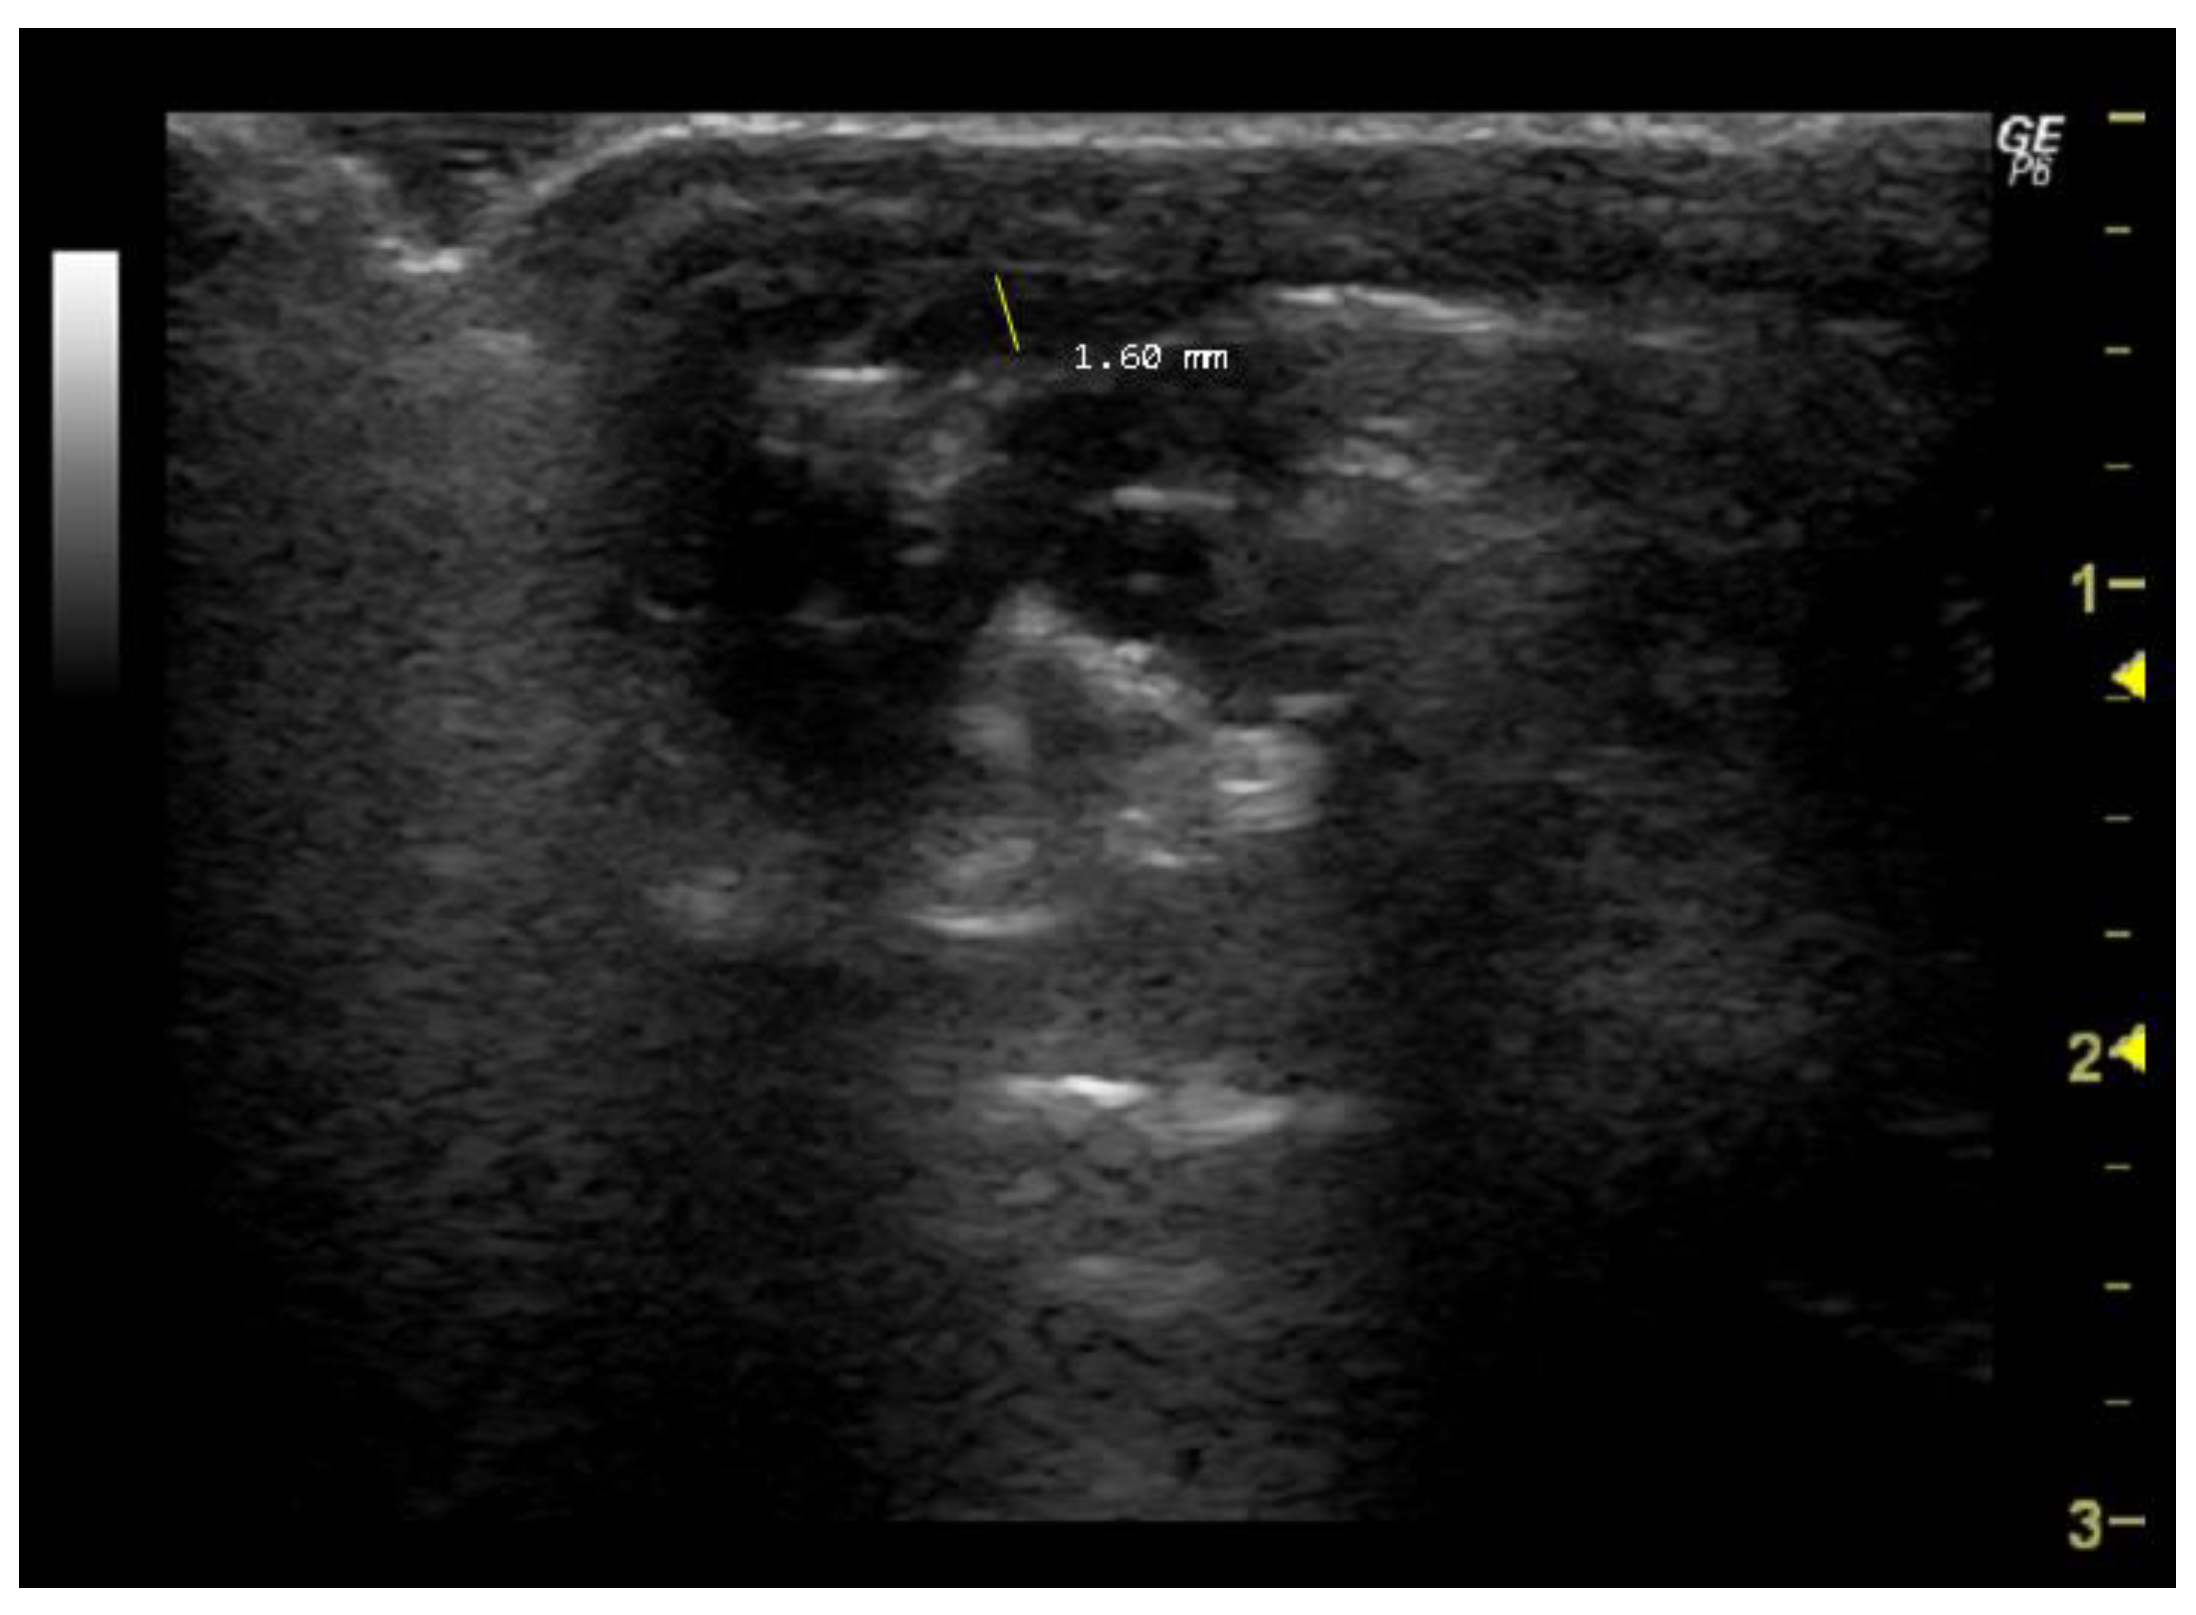

- How to measure Aod